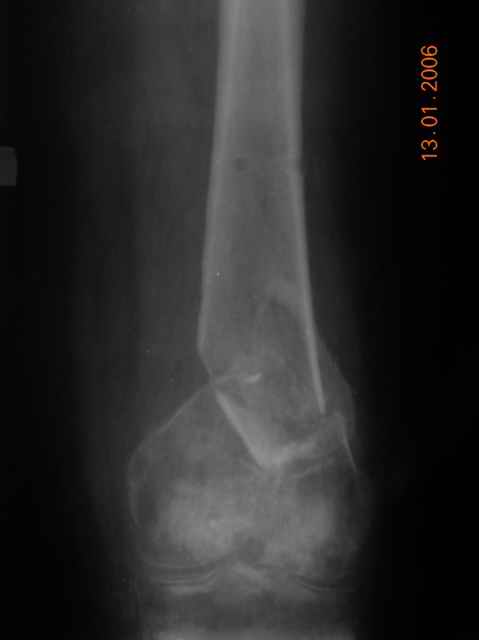

Несросшийся перелом дистального эпиметафиза бедра |

Уважаемые коллеги! Просим совета. Больная 50л лечилась АВФ по поводу оскольчатого перелома дистального эипметафиза левого бедра, по снятии приступила к разработке коленного сустава.

Через 6 месяцев в области перелома отмечается патологическая подвижность н/3 бедра. Задачи:1)добиться сращения;2)мобилизовать коленный сустав. При остеосинтезе планируется удлинить сухожилие четырехглавой мышцы. Можно ли решить поставленные задачи ретроградным ЗИО Chm? Сторонники пластины DCS считают, что при таком остеопорозе стабильности с ЗИО не будет,что не позволить приступить к ранней мобилизации, + необходима костная пластика, т.к. рассверливание метафиза должного эффекта не принесет.